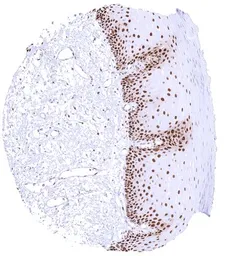

GTX644715 IHC-P Image

IHC-P analysis of human esophagus tissue using GTX644715 PCNA antibody [HMV4714] HistoMAX™.

In the squamous epithelium, nuclear PCNA staining is highest in suprabasal cell layers and markedly decreases towards the surface where PCNA staining is lacking.